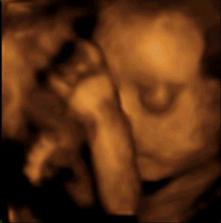

tak sme sa prehupli do tretieho trimestra - a čakame malu copaňu. Tešime sa na ňu.

14.12. je tesne pred vianocami a teším sa na ne. radosť mi ale skalila kolika na obličke ktorá ma doviedla až do nemocnice kam ma museli brať záchranári. našťastie maličká je ok a má 2300 gramov.